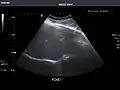

Right kidney -